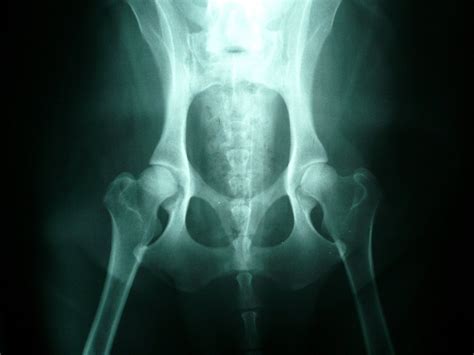

1. Dysplázia bedrových kĺbov (DBK)

Je dedičné ochorenie, pri ktorom zadné končatiny dobre nezapadajú do kĺbových lôžok, čo spôsobuje voľnosť kĺbového spoja a vedie k postupnej degeneratívnej artritíde bedrových kĺbov a k ich nehybnosti. Na dyspláziu bedrových kĺbov sú labradory náchylné a preto by ste si pri výbere šteniatka mali preveriť, aký stupeň DBK (0 - 4) mali rodičia šteniatka. Žiaden z rodičov by nemal mať stupeň DBK vyšší ako 1.